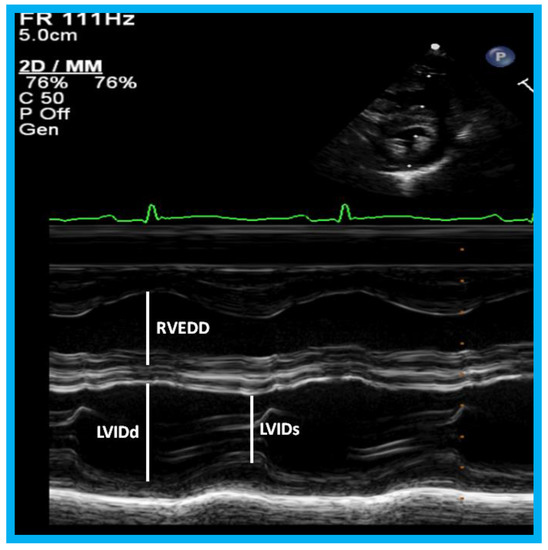

Figure 23. M-mode recording of the ventricles demonstrating measurements of left ventricular internal dimension in end-diastole (LVIDd) and right ventricular end-diastolic dimension (RVEDD), both measured at the onset of the QRS complex of the simultaneously recorded electrocardiogram (ECG): The left ventricular internal dimension in systole (LVIDs) is measured at end-systole. The data are compared with normal values, and z score is determined. These data are also used for calculation left ventricular fractional shortening: FS = {(LVIDd − LVIDs)/LVIDd} 100 (where FS is fractional shortening, LVIDd is left ventricular end-diastolic dimension, and LVIDs is left ventricular end-systolic dimension.) to assess the left ventricular systolic function.